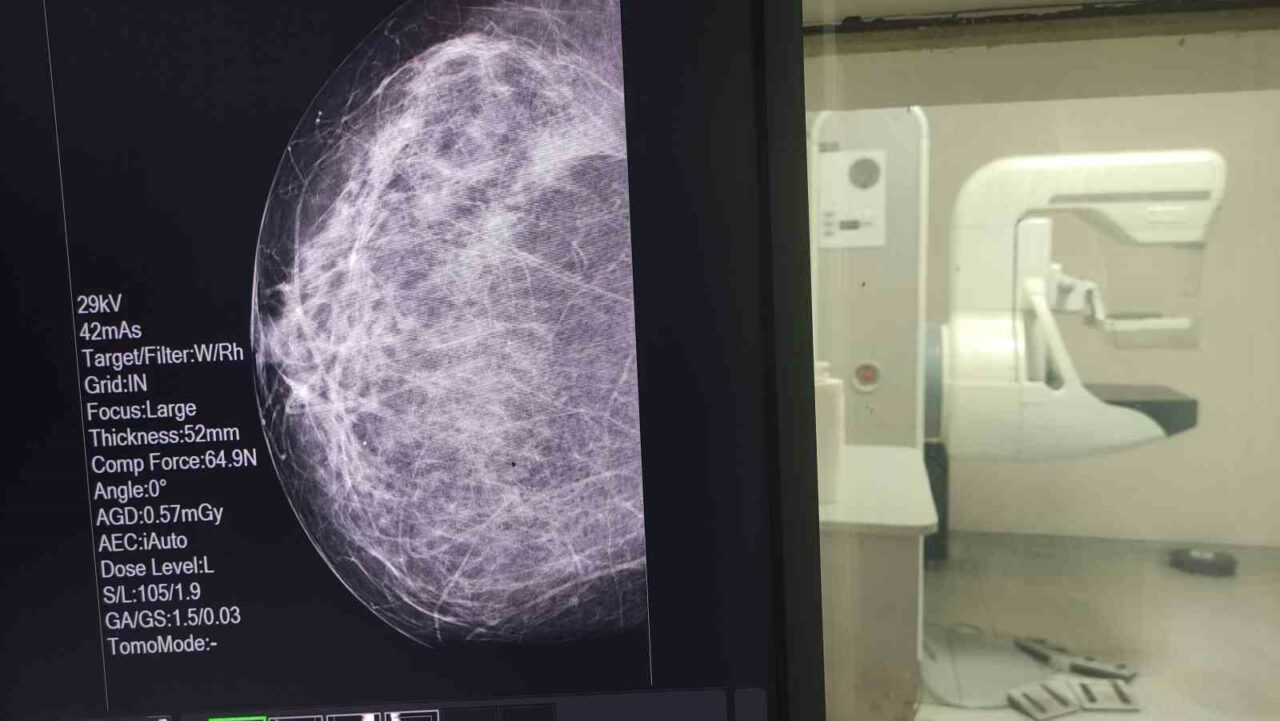

Sağlıklı hayat merkezi bünyesinde meme kanserine yönelik; taramaların, elle muayenenin ve erken teşhisin önemi gibi konularda vatandaşlara yönelik eğitimler gerçekleştirdiklerini vurgulayan Dr. Yavuz, “Kendim 47 yaşındayım bu sürece kadar 2 kere mamografim olması gerekirken ben bu mamografiyi çektirmedim. Araya korkularım girdi, kaygılarım girdi, hayatımdan önemli olmayan sebepler girdi. Bir gün röntgen teknisyeni arkadaşımızın ısrarı ile kaygılarımı, korkularımı bir kenara bıraktım. 5 dakikalık sürede gittim, mamografimi çektirdim” dedi.

Bu süreçte elle muayenede herhangi bir bulgu yaşamadığını dile getiren Dr. Yavuz, “Herhangi bir şikâyetim, semptomum da yoktu. Bana bir şey olmaz dedim ve ben mamografi çektirdiğimi unuttum. Ama görev yaptığım hizmet alanımda çekilen mamografi ile bana bi-rads 4c denilen meme kanseri öncesi tarama bulgusu tanısı konuldu. Ben bu tanıyla ileri tetkik ve tedavi yaptığımda meme kanseri ile karşılaştım” şeklinde konuştu.

Çektirdiği mamografi sayesinde erken tanı aldığını ve tedavisini tamamladığının altını çizen Dr. Yavuz, “Şu anda hayatıma sağlıklı olarak devam ediyorum. İşte o beş dakika benim tüm hayatıma yön verirken, çok olumlu sonuçlara sebep oldu. Her ay yapacağınız bir elle meme muayenesi sizin hayatınızı tanımanızda, çektireceğiniz mamografi de tanınızın erken olmasına sebep olacak. Ben hekim olarak bunu yaptım. Kendi birimimde bunu başarabildim. Sizleri de her zaman KETEM birimlerinde mamografinizi çektirmeye davet ediyoruz” ifadelerini kullandı.